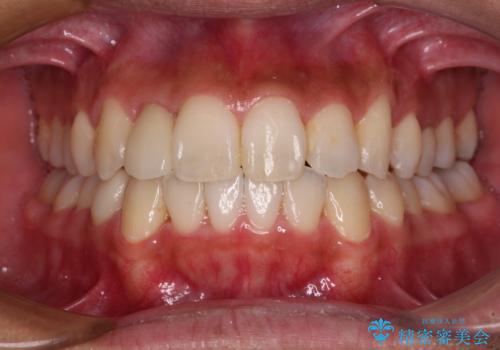

【モニター】左右のクロスバイトをインビザラインできれいに改善

【モニター】八重歯と前歯のクロスバイト ワイヤーを併用しインビザラインで矯正治療